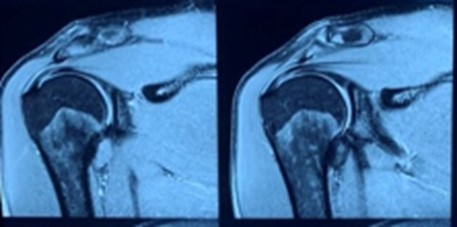

Van Toan chan thuong anh 2

Phim MRI khi có tiêm thuốc cho thấy tổn thương rõ hơn.